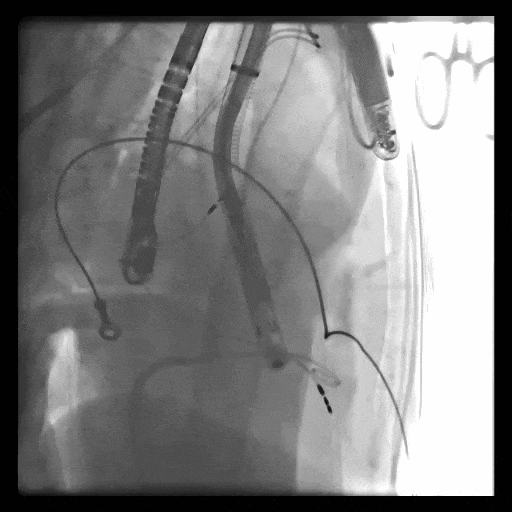

術中DSA顯示起搏器導線的干擾,右心室造影確定瓣環位置,操作空間小